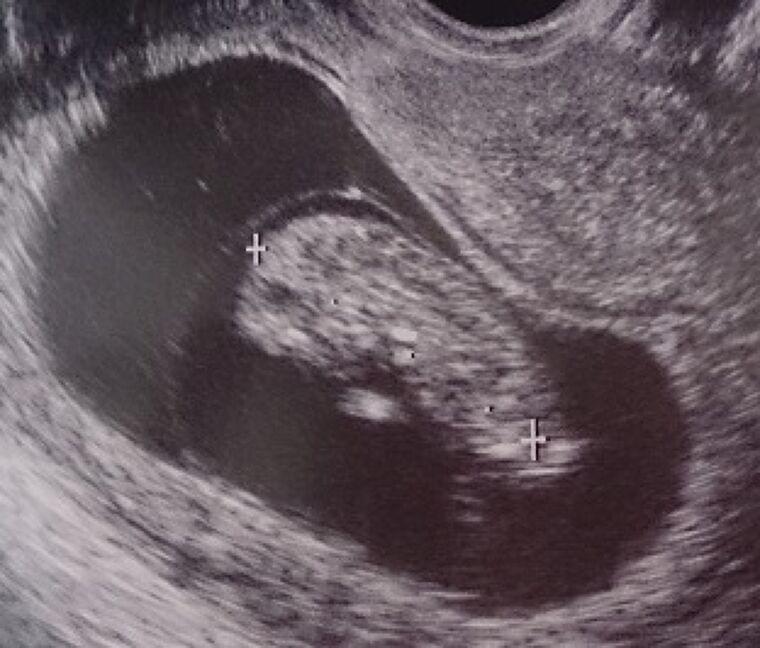

妊娠に気が付く前、妊娠初期から胎児の発育は始まっています。妊娠初期は大切な時期であり、妊娠前の低体重や葉酸摂取不足、偏った食生活、喫煙・飲酒の習慣等が胎児の発育と、赤ちゃんの将来の健康に大きく影響するといわれています。